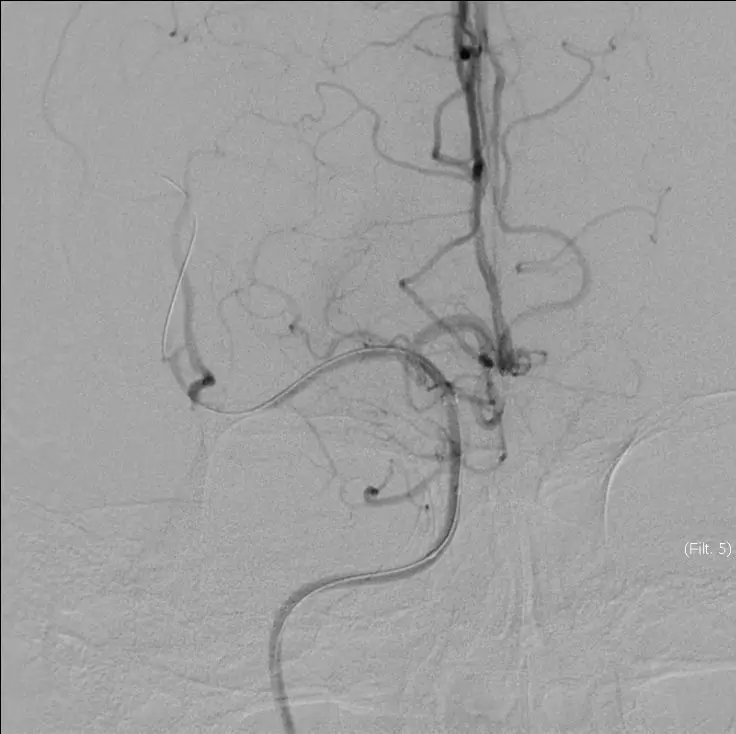

赛诺 2.0*15mm球囊扩张

5MIN后

赛诺 2.0*15mm球囊扩张

5MIN后

10MIN后

再次与家属沟通病情,交代支架植入风险,家属表示理解,准备支架解脱

5MIN后

再次观察10MIN后